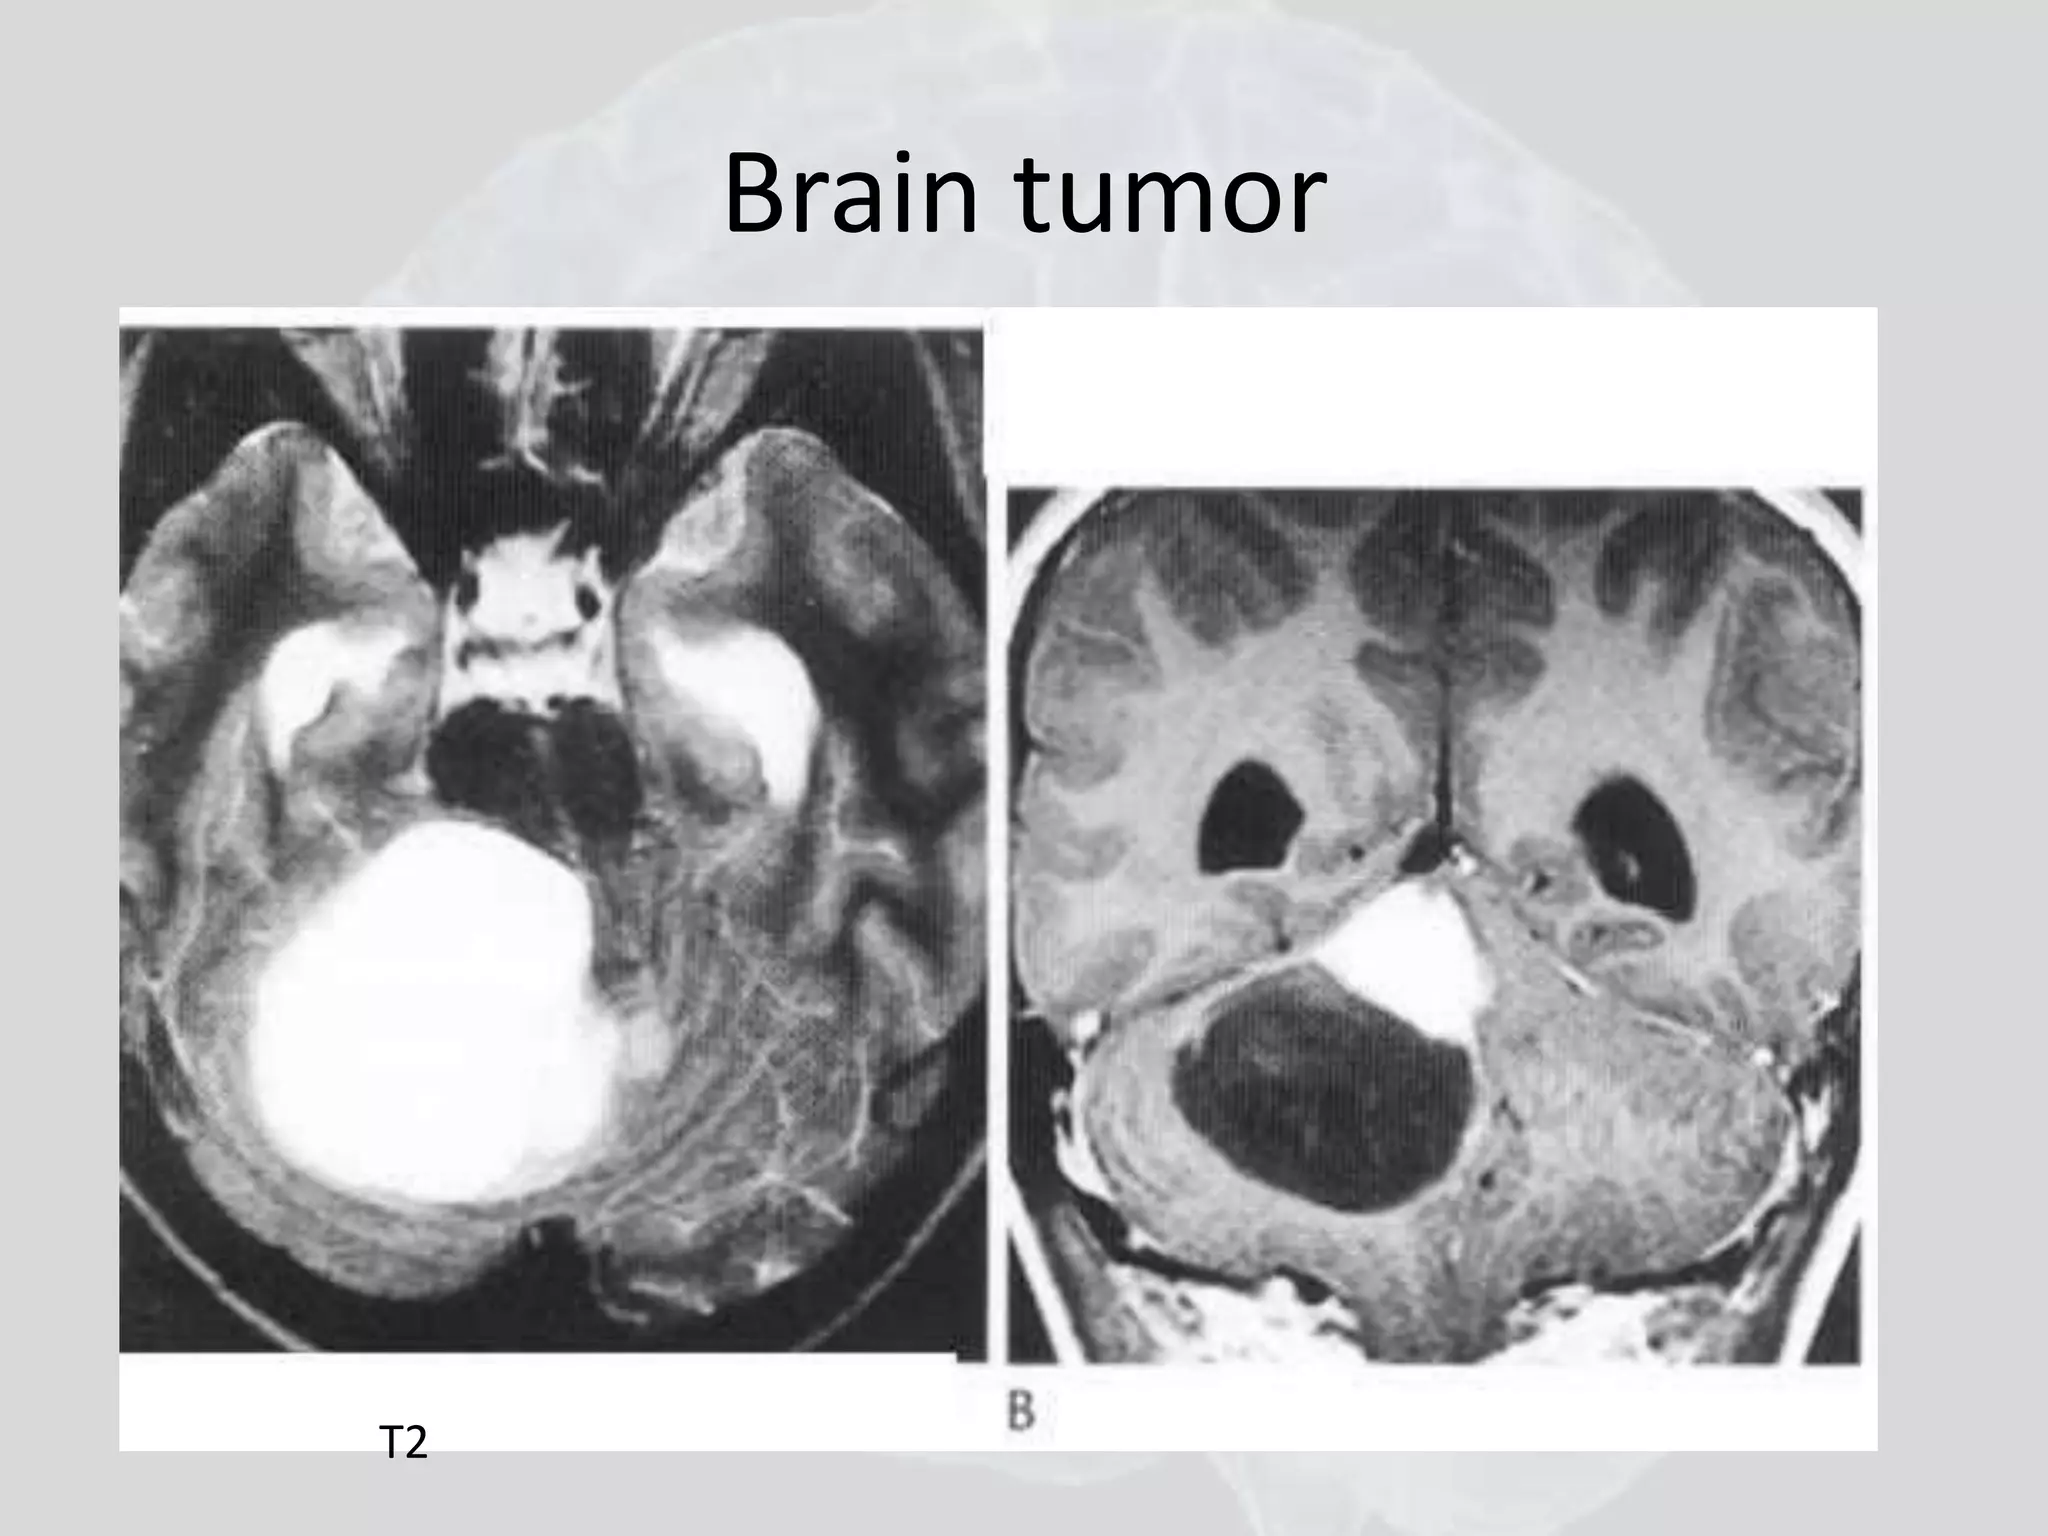

Brain tumors

• High-grade or malignant gliomas appear as

contrast-enhancing mass lesions, which arise

in white matter and are surrounded by edema

• Multifocal malignant gliomas are seen in ~ 5%

of patients.

• Low-grade gliomas typically are nonenhancing

lesions that diffusely infiltrate brain tissue and

may involve a large region of brain.

• Low-grade gliomas are usually best

appreciated on T2-weighted MRI scans.

Brain tumor

T2